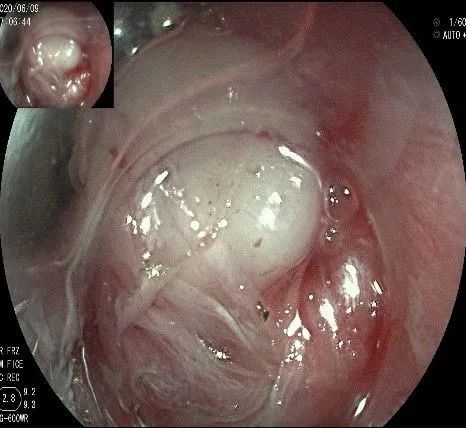

倒镜观察,可见贲门部一个明显的隆起,中央部分的凹陷,是4天前取活检留下的。

我们的思路:病变长径约2.0cm,位置活动,倒镜后先在胃底侧粘膜下注射,使病变向食管腔方向抬举,然后再在食管腔内做粘膜下注射切开,以获得一个好的术野,果然,注射后粘膜抬举明显,瘤体被挤向口侧。

正镜观察,瘤体就在贲门部齿状线的下方。